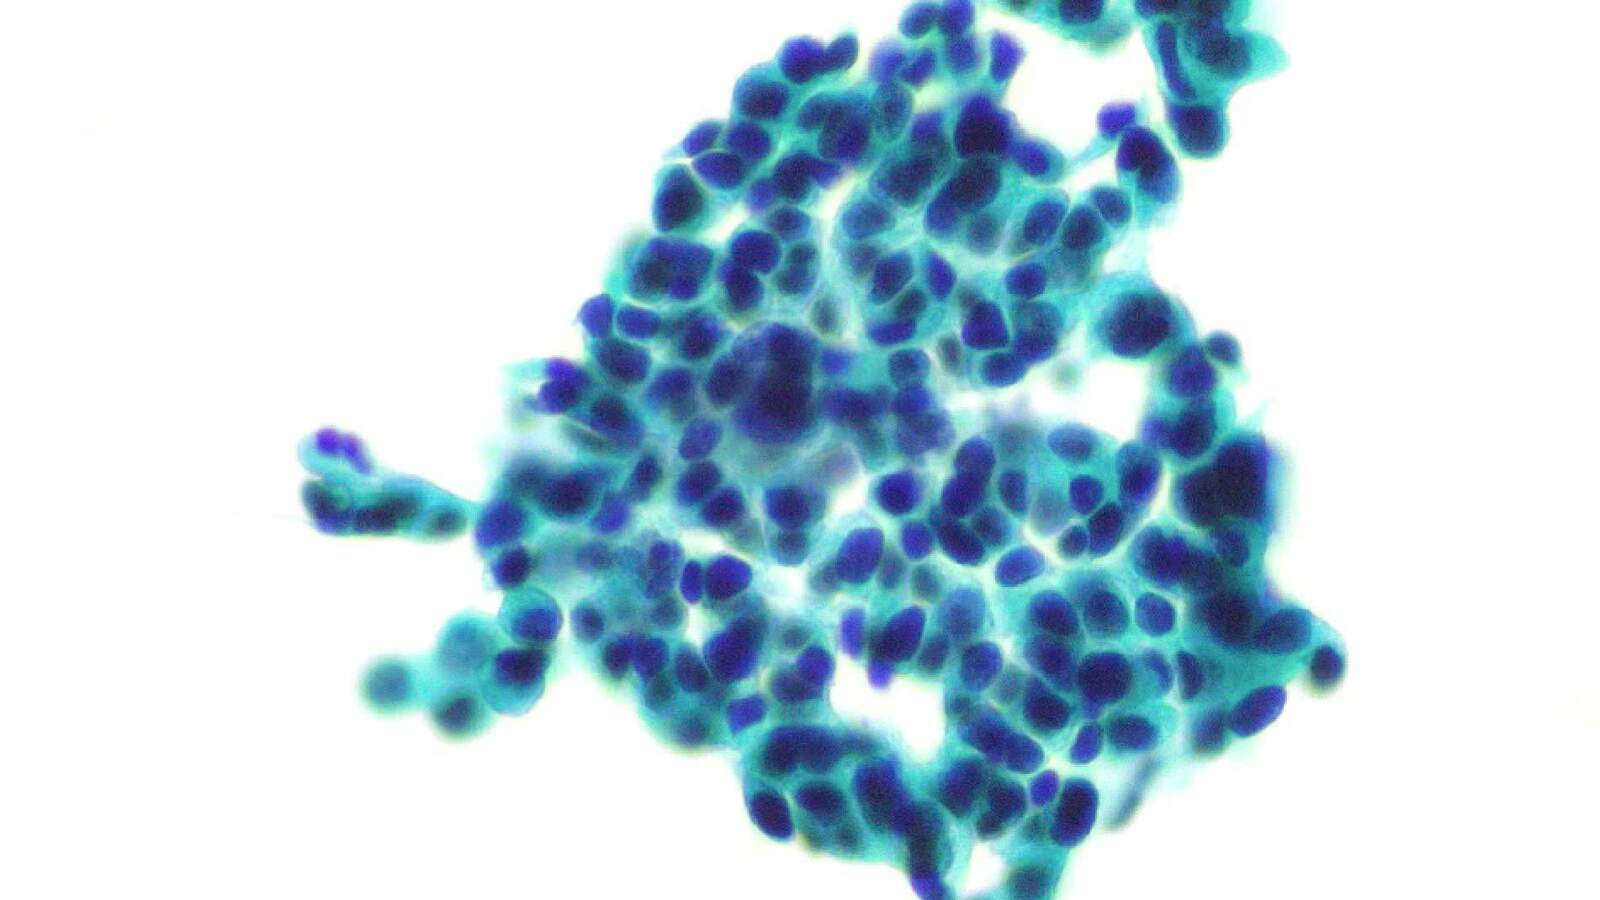

明场观察方式在多个学科领域都发挥着不可或缺的作用。在生物学领域,它常被用于研究细胞、组织、细菌等生物样本的微观结构和功能。在医学领域,明场观察则是病理学检查、临床实验室检测和血液分析等工作的重要辅助手段,为医生提供了宝贵的诊断依据。此外,在材料科学、环境科学等领域,明场观察同样发挥着重要作用,有助于研究人员深入了解材料的微观结构和性质。

应用领域:常规镜检、病理、染色标本